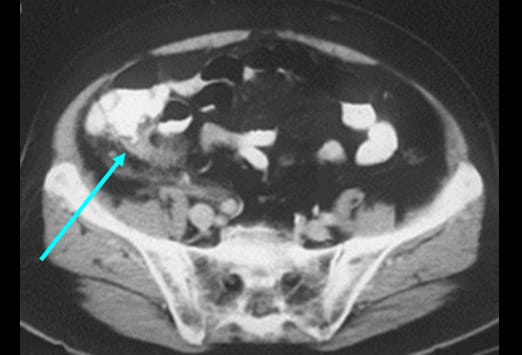

Eine atypische Appendizitis (siehe Abbildung) stellt eine diagnostische Herausforderung dar. Dieser 54-jährige Mann hatte seit 2 Tagen periumbilicale Schmerzen, eine Leukozytose und eine Abwehrspannung im Mittelbauch. Die CT-Untersuchung ergab den Befund einer Malrotation des Kolons mit einer Appendizitis (Pfeil) im Bereich des linken Oberbauchs. Man beachte den perityphlitischen Abszess. Trotzdem verursacht eine Appendizitis typischerweise Schmerzen im Bereich des rechten Unterbauches. Dies ist wichtig bei der raschen Erhebung einer Differentialdiagnose.